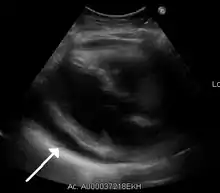

| A 2D echo transthoracic echocardiogram of pericardial effusion. The "swinging" heart. | |

ECG: may present with sinus tachycardia, low voltage QRS as well as electrical alternans.[2] Due to the fluid accumulation around the heart, the heart is further away from the chest leads, which leads to the low voltage QRS. Electrical alternans signifies the up-and-down change of the QRS amplitude with every beat due to the heart swinging in the fluid (as displayed in the ultrasound image in the introduction) .[1] These three findings together should raise suspicion for impending hemodynamic instability associated with cardiac tamponade.

Echocardiogram (ultrasound): when pericardial effusion is suspected, echocardiography usually confirms the diagnosis and allows assessment of the size, location and signs of hemodynamic instability.[4] A transthoracic echocardiogram (TTE) is usually sufficient to evaluate pericardial effusion and it may also help distinguish pericardial effusion from pleural effusion and MI. Most pericardial effusions appear as an anechoic area (black or without an echo) between the visceral and the parietal membrane.[1] Complex or malignant effusions are more heterogeneous in appearance, meaning they may have variations in echo on ultrasound.[5] TTE can also differentiate pericardial effusion based on the size. Although it's difficult to define size classifications because they vary with institutions, most commonly they are as follows: small <10, moderate 10–20, large >20.[5] An echocardiogram is urgently needed for evaluation when there is concern for hemodynamic compromise, a rapidly developing effusion or history of recent cardiac surgery/procedures.[1]